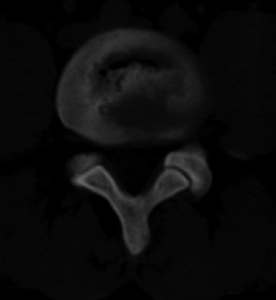

男,20,士兵,腰痛3年多,无外伤史

倒数7~9幅图像示椎体后缘双边征及双关节征,支持l5轻度滑脱。

1、多发许莫氏结节。

2、腰5双侧椎弓峡部崩裂并i度前滑脱,楼主椎间盘扫描角度有问题,另外需要反倾角扫描腰5椎弓峡部。

2、腰5双侧椎弓峡部崩裂并i度前滑脱。